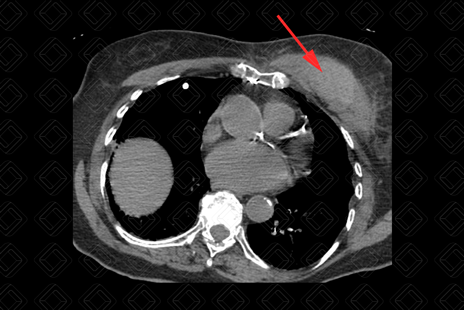

Texto alternativo para a imagem Figura 3. Créditos: Dra. Elazir Mota - Rio de Janeiro/RJ

Descrição das figuras 1, 2 e 3: Tomografia computadorizada de tórax evidenciando lesão heterogênea (seta vermelha) na musculatura peitoral esquerda, espontaneamente densa (densidade ao redor de 65 UH), compatível com hematoma. Paciente fazia uso crônico de anticoagulante.

• Tomografia computadorizada (TC): Observamos aumento volumétrico da musculatura acometida e conteúdo espontaneamente denso no estudo sem contraste (50-80 UH) (figura 1);